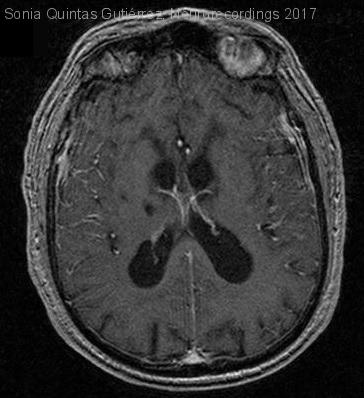

Hombre | 83 años

Diagnóstico final: Carcinomatosis meningea

Varón de 83 años, con hipertensión arterial, dislipemia y diabetes mellitus. Ingresó por cuadro progresivo de dos semanas de somnoliencia. No había presentado fiebre ni sintomatología infecciosa. Refería desde hacía 3 meses astenia e hiporexia progresivas. En...